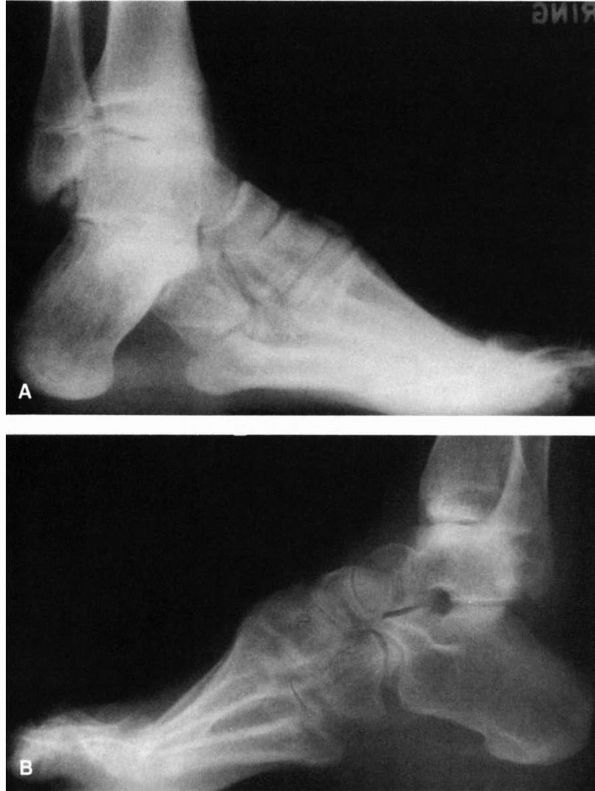

![]() |

|

FIGURE 21-24. Radiographs of the cavus foot. (A) Marked dorsiflexion pitch of the calcaneus. Normal calcaneal pitch is 20 to 40°. (B)

Forefoot equinus resulting in a cavus foot. Note the almost normal-appearing pitch to the calcaneus. (Mann RA, Coughlin MJ. The Video Textbook of Foot and Ankle Surgery. St Louis: Medical Video Productions, 1991) |